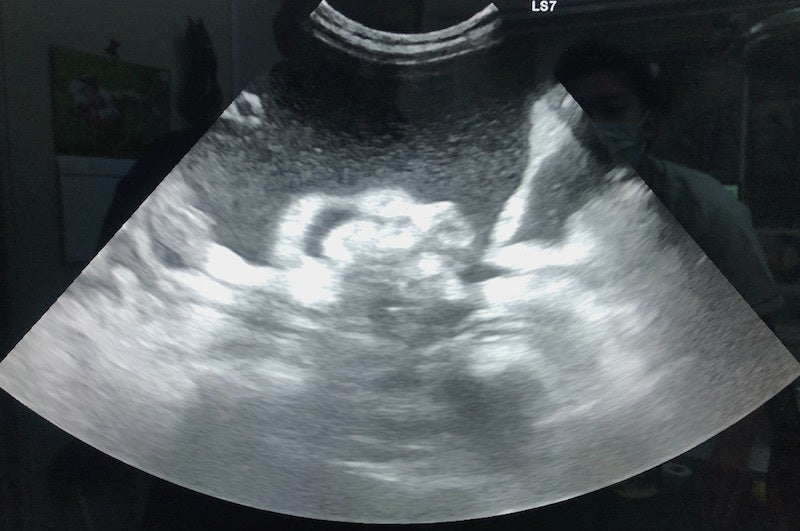

FIPという診断を受けた時に、あらゆる手段を使いこの病気について調べました。動物病院の先生やネットで調べた結果、外猫・野良猫のほとんどが持っているコロナウイルスが突然体内で変異し、FIPウイルスになるということが分かりました。FIPウイルスは一度発症してしまうと元に戻ることはありません。原因はストレスのことが多いと言われており、ずら丸にストレスを与えてしまっていたと日々嘆くばかりです。現在の症状としては腹水・胸水の貯留、食欲減退、便秘、黄疸、脱水症状です。動物病院への通院で脱水症状については収まりを見せていますが、その他は改善の兆しが見えてきません。

腹部エコー画像

ずら丸の腹水が溜まっているのを見た際、リンパ癌や心臓の病気など様々な病気を疑いました。しかし考えていたよりも状況は重く、不治の病と言われるFIPでした。世界中にFIPで苦しんでいる猫、オーナー様はいらっしゃいます。新薬での寛解を実証出来れば、今後のオーナー様のFIP治療の選択肢が広がるのではないかと考えています。